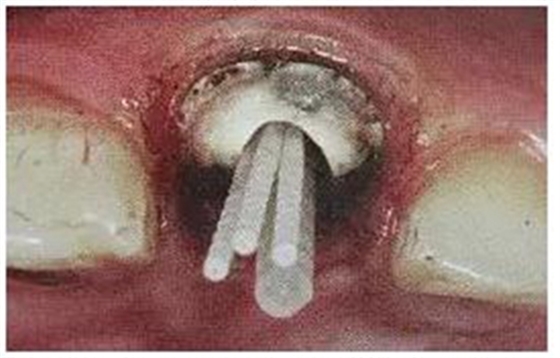

13.不規(guī)則根管的纖維樁粘接

普通纖維樁對圓形截面的根管適合性較好,面對不規(guī)則時(shí)(橢圓形、喇叭形等)根管適應(yīng)性差,難以取得好粘接和修復(fù)效果。

(輔樁的運(yùn)用)

輔樁的運(yùn)用可改善這些適應(yīng)性的問題。